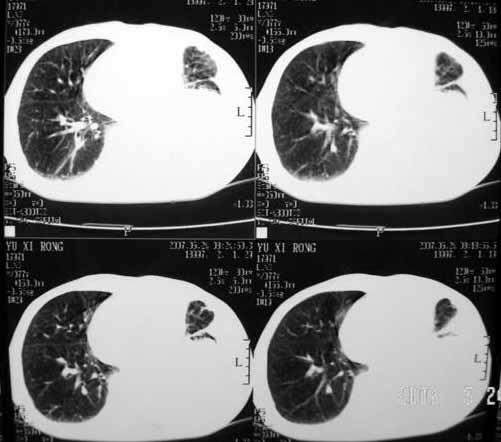

以下是引用luochengyi在2007-5-24 14:33:00的发言:[br]考虑左下肺癌。左侧胸腔积液。

以下是引用adams在2007-5-24 17:12:00的发言:[br]支持“考虑左下肺癌,左侧胸腔积液,建议胸水检查”。[br] [br]

以下是引用fumaogui在2007-5-24 16:20:00的发言:[br]左侧胸腔积液.[br]左下叶不张考虑中心型肺癌[br]建议纤支镜检查.